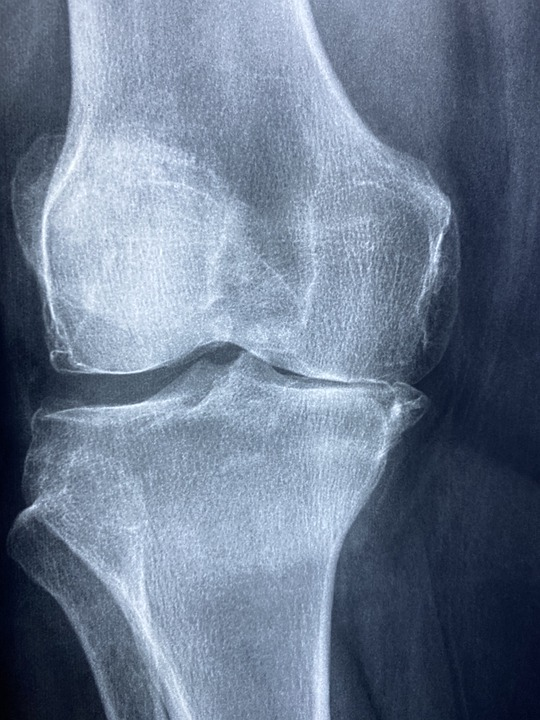

Credit: North County Orthopedic Medical Group